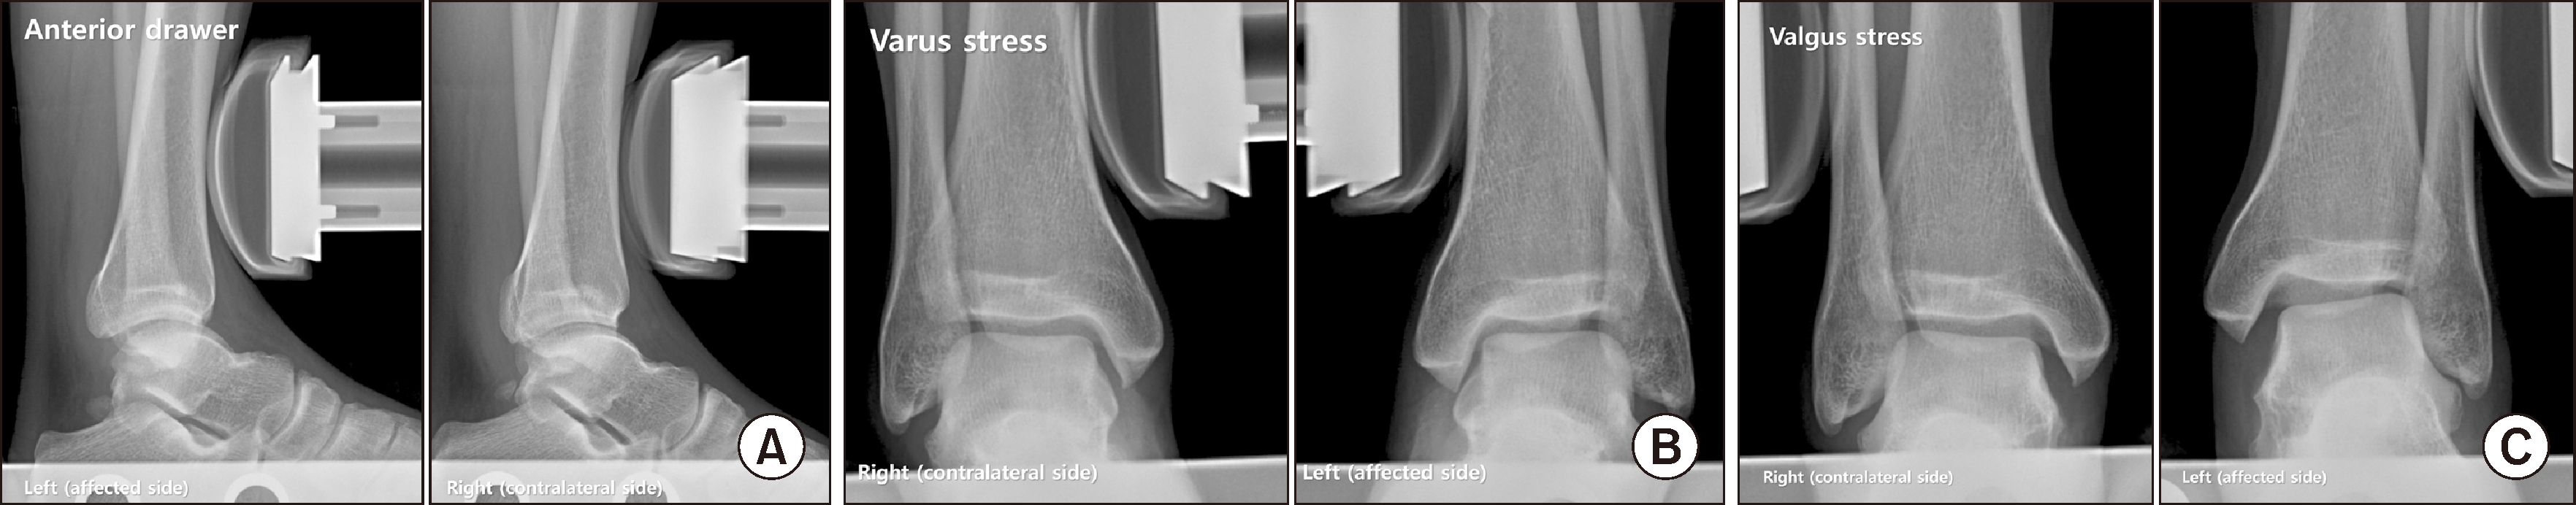

Figure 2

Stress radiographs using the Telos device (METAX). Anterior drawer radiograph (A) revealed 10 mm of anterior talar translation, which was 3 mm greater than the contralateral side and varus stress radiograph (B) showed a 1.9º varus tilt of the talus. Valgus stress radiograph (C) demonstrated a 10.4º valgus tilt of the talus, which showed an increase of approximately 7º compared to the weight-bearing anteroposterior radiograph.

통증 및 압통의 부위를 고려하였을 때 다발성 인대 손상이 의심되었기에, 관절 불안정증 여부를 보다 구체적으로 확인하기 위하여 여러 종류의 부하 방사선 검사를 시행하였다. Telos 장비(METAX)를 이용한 전방 당김 검사에서 거골의 10 mm 전방 당김이 관찰되었고(Fig. 2A, 반대측보다 3 mm 큼), 내반부하 검사에서는 1.9°의 내반거골 경사가 확인되었다(Fig. 2B). 외반부하 검사에서는(Fig. 2C) 10.4°의 외반거골 경사가 측정되어 체중부하 전후면 방사선 사진에 비하여 약 7°의 외반거골 경사 증가를 확인할 수 있었다. 내원 1달 전 타병원에서 촬영한 족관절 자기공명영상 검사에서, 삼각인대가 내과 부착 부위에서 신호 강도가 옅어지면서 연결성이 불분명해졌기에 이 부위에서의 파열이 의심되었으며(Fig. 3A), 전하경비인대 및 종비인대의 손상 여부는 명확하지 않았으나, 전거비인대는 비골 부착 부위 근처에서 파열되어 연결성이 소실되어 있었다(Fig. 3B). 마지막으로 만성 골간인대결합 손상 여부를 확인하기 위하여 촬영한 족관절 컴퓨터 단층촬영상, 골간인대결합(syndesmosis) 위치의 비골구(incisura fibularis) 내에 비골이 전방으로 치우쳐진 채로 위치하고 있는 모습을 확인할 수 있었다(Fig. 3C).